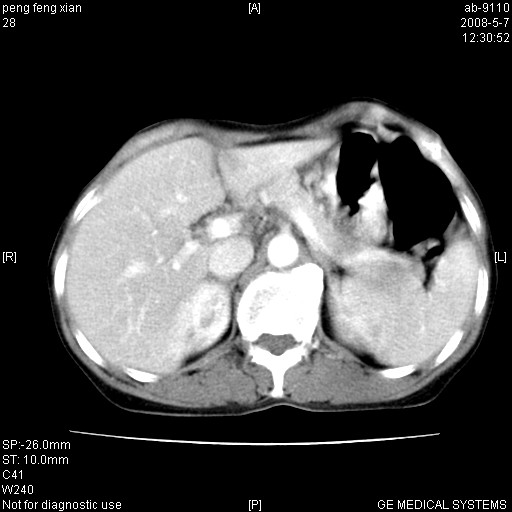

女,56岁。b超左一腹包块,考虑胃肠道肿瘤。

胃壁增厚,左前胸壁局限性隆起,考虑胃癌可能性大,建议做胃镜

典型胃癌胰体尾部受侵。

胃体部胃壁增厚,不均匀性强化,与胰腺分解欠情.

考虑:胃癌,胰腺受侵待除外.

鉴别:胃淋巴瘤(强化不明显)

建议:胃镜检查.